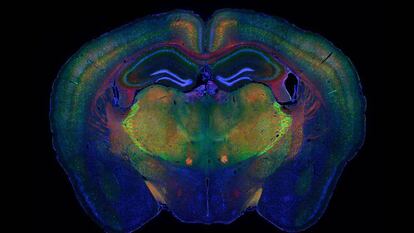

Estas técnicas, cuyo uso se ha universalizado desde 2013, permiten saber qué genes están activos en una célula, conocer su función, ponerle una etiqueta para seguirla a lo largo de su vida y ver cómo interactúa con otras células en un plano tridimensional. Así se puede observar cómo un embrión de unas pocas células da lugar a los diferentes órganos hasta generar un individuo sano o desvelar los procesos moleculares que originan el cáncer y otras enfermedades.

Hace unos cinco años estas técnicas permitían secuenciar como mucho cientos de células a la vez; ahora ya se pueden analizar varios cientos de miles. Esto permite caracterizar órganos completos e incluso organismos enteros. Una de las aplicaciones de esta tecnología es encontrar nuevos tipos de células en el cuerpo humano. Este año se ha descubierto una nueva clase de células presentes en la zona de contacto entre útero y placenta que realizan una labor de mediación con el sistema inmune de la madre para que este reconozca al feto y no lo ataque durante los primeros meses de gestación. Lo mismo ha sucedido en el cerebro o el sistema respiratorio.

“Si antes pensábamos que había unos 3.000 tipos diferentes de células en el cuerpo humano, ahora creemos que hay 10 veces más”, explica Holger Heyn, investigador del Centro Nacional de Análisis Genómico, en Barcelona, y uno de los coordinadores del proyecto Atlas Celular Humano. Esta iniciativa, que surgió en 2016 y que involucra a más de 1.000 equipos científicos de 58 países, aportará el primer mapa celular de 10 órganos humanos en 2022. “Estas técnicas nos van a dar un Google Maps del cuerpo humano completo en el que podremos hacer zoom en cada órgano y explorarlo célula a célula. Primero tendremos una referencia de un cuerpo sano y después se irán añadiendo perfiles específicos de enfermedades", explica.